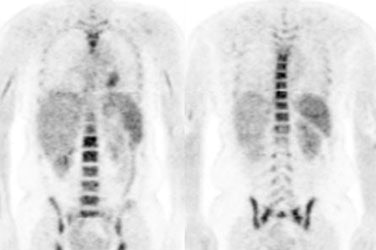

Hyperinsulinemia: The patient below had

a normal glucose level and was injected for an FDG PET

scan. Imaging revealed intense cardiac uptake and a large

about of muscular activity. The findings are consistent

with a hyperinsulinemic state and the patient subsequently

admitted to eating a small breakfast. |